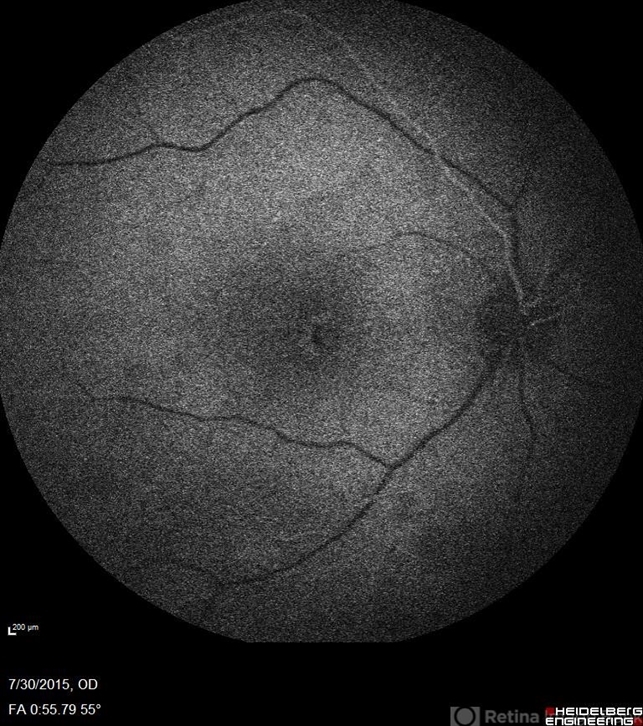

- Goldmann-Favre Syndrome, juvenile retinoschisis, retinal dystrophy

- Fluorescein angiography of a 24-year-old male. Juvenile retinoschisis on OCT. FA shows outer retinal staining. Could be associated with Goldmann Farve Syndrome.